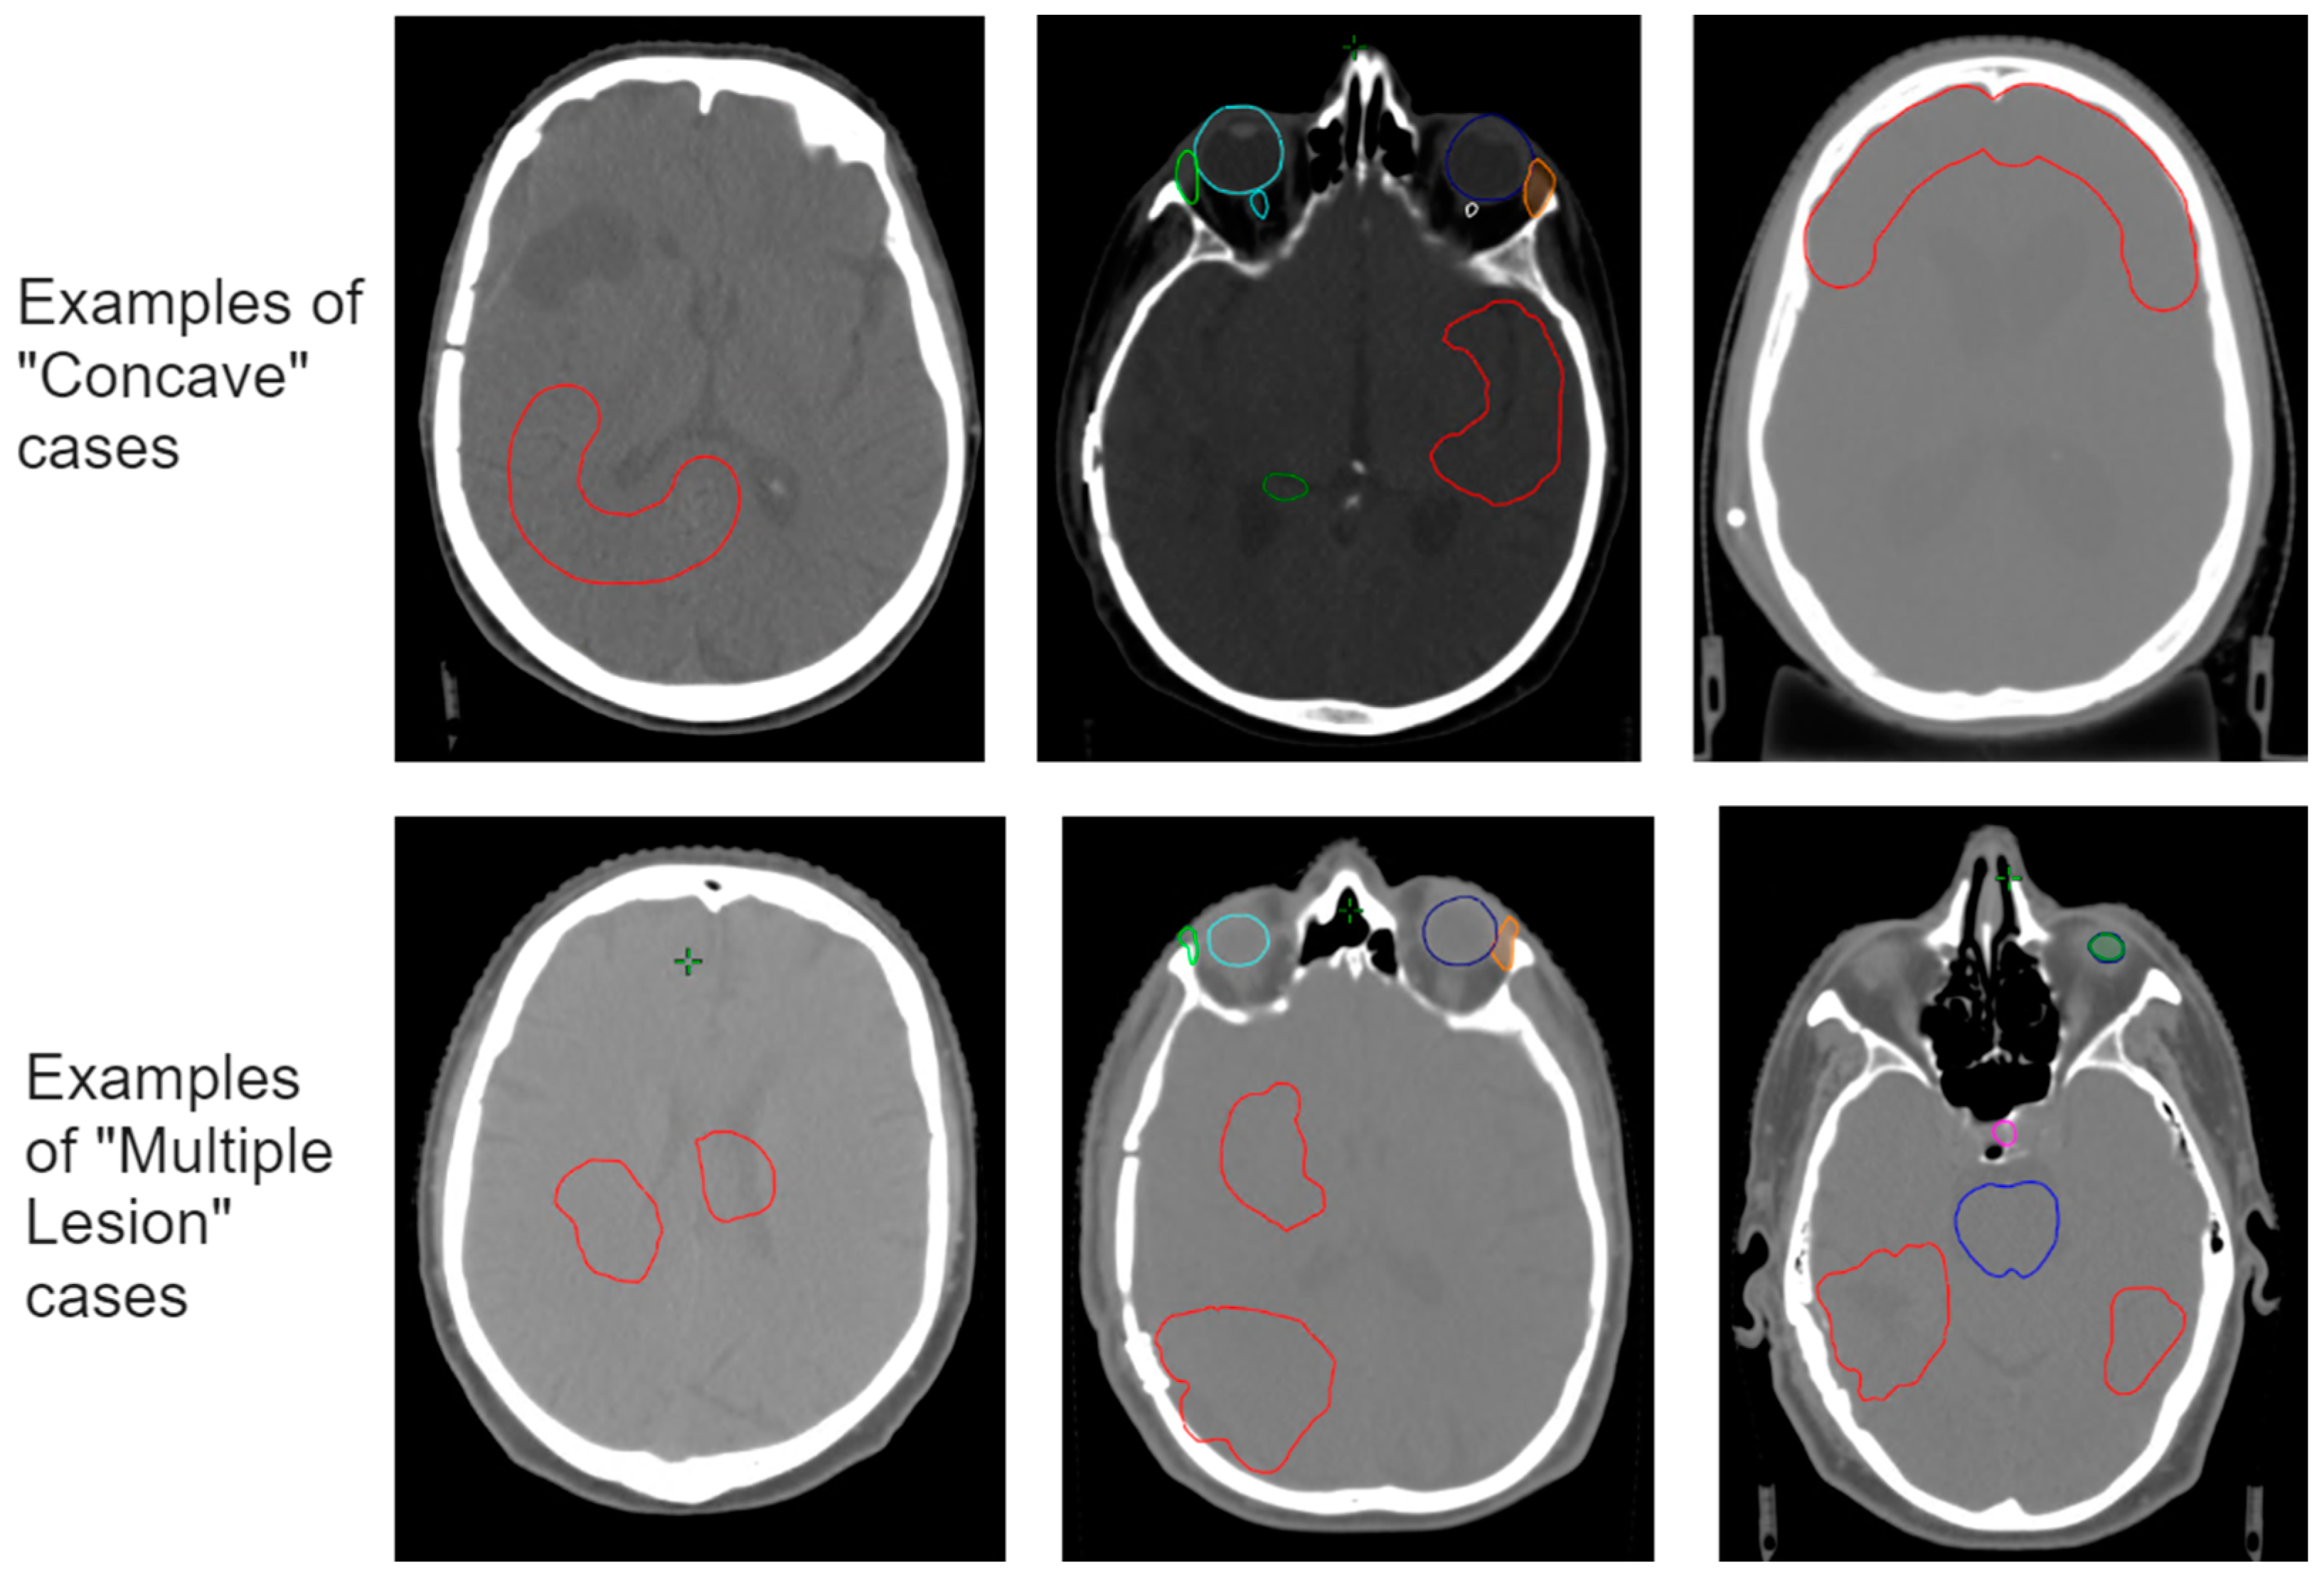

2.5. Improving the Model–Worst-Case Test Set

3.2. Improving the Model–Worst-Case Test Set